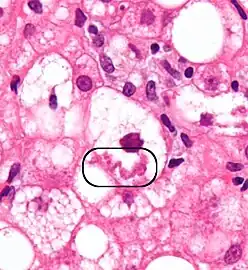

A small quantity of tissue is sampled from the liver when doing a biopsy, which is then examined under a microscope

Micrograph of non-alcoholic fatty liver disease, demonstrating marked steatosis (fat in liver cells appears white; connective tissue, blue). Trichrome stain

A liver biopsy (tissue examination) is the only test widely accepted (gold standard) as definitively diagnosing and distinguishing NAFLD (including NAFL and NASH) from other forms of liver disease and can be used to assess the severity of the inflammation and resultant fibrosis. However, since most people affected by NAFLD are likely to be asymptomatic, liver biopsy presents too high a risk for routine diagnosis, so other methods are preferred, such as liver ultrasonography or liver MRI. For young people, guidelines recommend liver ultrasonography, but biopsy remains the best evidence.[5][7][63][27] Liver biopsy is also the gold standard to detect hepatic fibrosis and assess its progression.[67] Routine liver function blood tests are not sensitive enough to detect MAFLD, and biopsy is the only procedure that can reliably differentiate NAFL from NASH.[16]